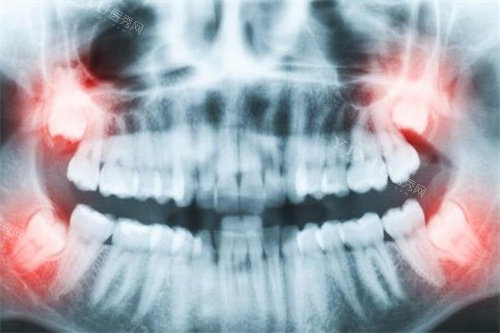

许多家长误以为乳牙迟早要换,出现问题不必治疗,这是重的误区。乳牙的健康直接影响恒牙发育和颌面生长。乳牙龋坏可能导致恒牙萌出异常,甚至影响孩子的营养摄入和语言发育。

迪士尼周边可靠儿童牙科诊所都强调乳牙治疗的重要性。通过早期干预,可以避免许多后续复杂问题,为孩子赢得更健康的牙齿未来。